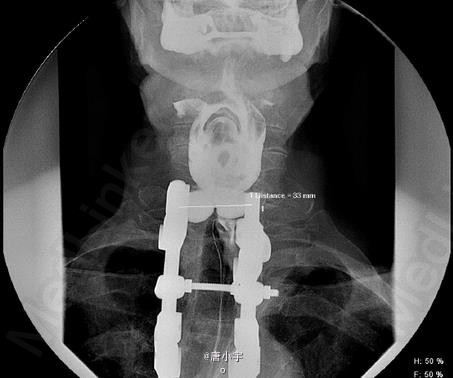

临床一例双叶食管憩室

患者,男,79岁,因进行性固体食物吞咽困难前来就诊。心脏病和陈旧性肝脓肿病史

双叶食管憩室 处理:手术切除